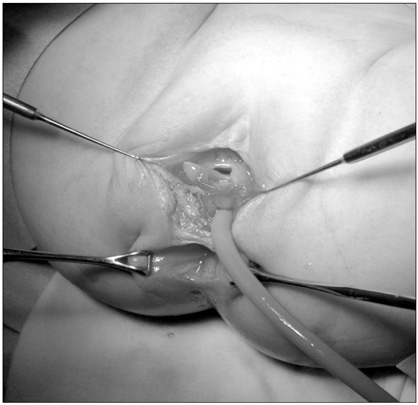

A 2-month-old female infant presented to our hospital with a 1-month history of stool passing through the vagina. She was born at 36 weeks' gestation weighing 1.875 kg and was the second infant of a twin. She had a ventricular septal defect that closed spontaneously at 1 month of age. Initially, she was diagnosed with a rectovaginal fistula. Despite conservative therapy, including a sitz bath, for 5 months, there was no improvement in her symptoms, and most of the stool still appeared to pass through the vagina. A colon study indicated a rectovaginal fistula directly connected to the distal rectum (

Fig. 1A preoperative colon study appeared to show that the contrast had passed to the vagina through a rectovaginal fistula (arrows).